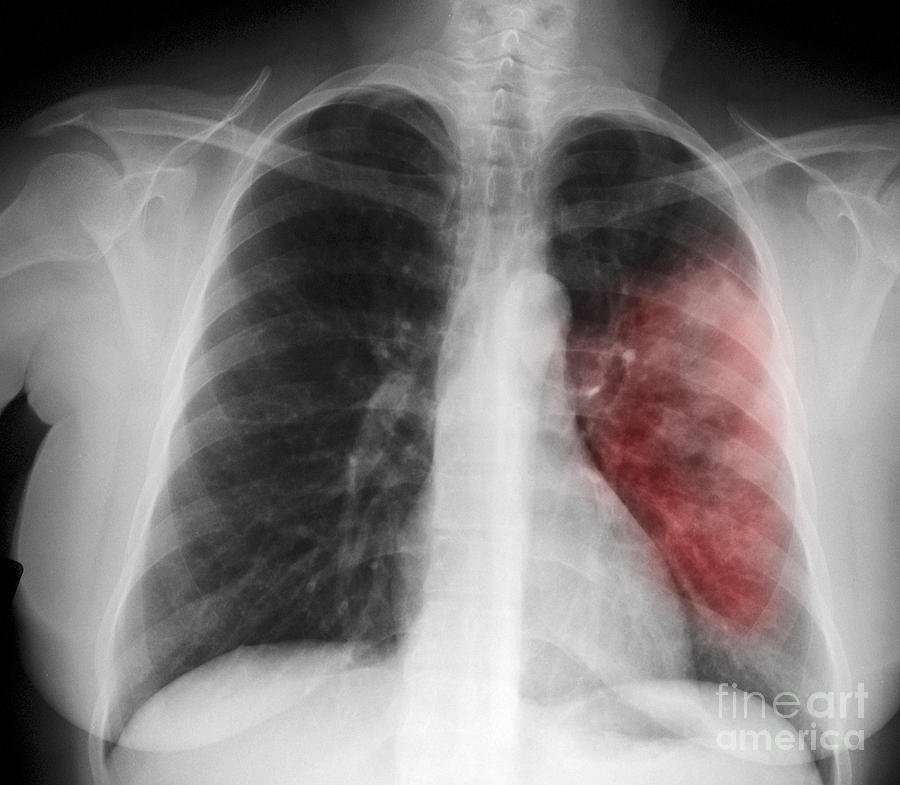

Симптомы и причины скопления воды в легких

Раздел: Ракурсы просвещения